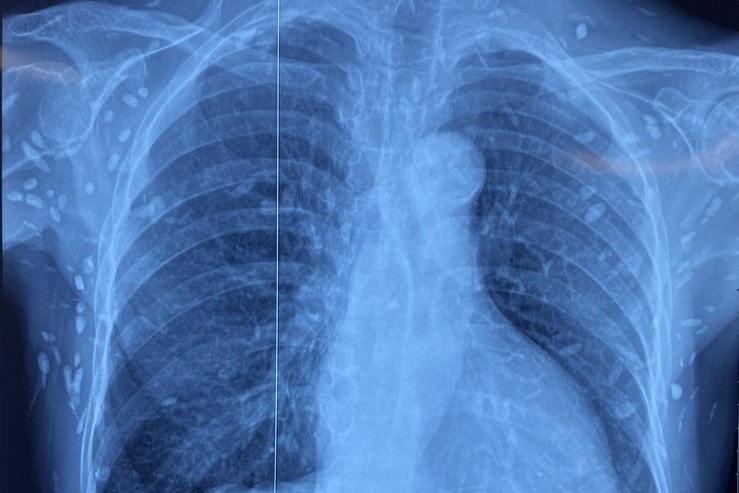

Bệnh nhân được chuyển lên từ tuyến trước trong tình trạng rối loạn ý thức, đe dọa suy hô hấp. Hình ảnh cắt lớp vi tính sọ não và X-quang ngực cho thấy rất nhiều nốt cản quang trong nhu mô não và dưới da vùng ngực - bụng. Một số u cục có thể sờ thấy dưới da vùng ngực và cánh tay.

Mặc dù xét nghiệm kháng thể IgM với sán dây lợn âm tính, song các tổn thương trên hình ảnh X-quang gợi ý người bệnh đã từng nhiễm ấu trùng sán dây lợn.

Nhiều nốt cản quang dưới da thành ngực, bụng và chi trên. Ảnh: BVCC

Theo thời gian, nang sán có thể thoái hóa hoặc vôi hóa, tạo nên nhiều nốt cản quang trên phim X-quang như trong trường hợp trên.